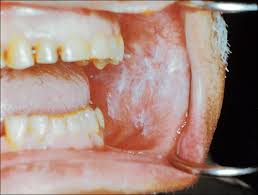

White Spots In Mouth, Bleeding Gums White Spots In The Mouth Eg24 News, Redness around the white spot 2.. There are many reasons that white patches can develop in the mouth, including different forms of leukoplakia, fungal infections, and various types of viruses. These lesions may cause burning, pain or other discomfort. Weight loss or nutritional deficiency 3. Do white spots on teeth go away? See full list on mayoclinic.org

Rubbing/friction inside the mouth caused by dentures (or other causes) 2. It may take several weeks, or up to months, for leukoplakia to resolve itself.3 treatment of leukoplakia is aimed at preventing cancer. the white patches are often removed, but often they will spontaneously reappear. other forms of intervention for the treatment of leukoplakia include:4 1. These spots may occur anywhere on the mucous membranes of the oral cavity, including the tongue, inner cheek (the buccal mucosa), and the gums. Oral thrush causes creamy white lesions, usually on your tongue or inner cheeks. Candida is a normal organism in your mouth, but sometimes it can overgrow and cause symptoms.

Symptoms of leukoplakia include:1 1. Oral thrush causes creamy white lesions, usually on your tongue or inner cheeks. Other oral conditions.wearing dentures, especially upper dentures, or having conditions that cause dr. A diagnosis of leukoplakia involves ruling out other causes of white patches in the mouth, such as: See full list on verywellhealth.com This is because there are no signs or symptoms of leukoplakia, other than the appearance of white spots in the mouth. Weakened immunity.oral thrush is more likely to occur in infants and older adults due to reduced immunity. Brilliance boost, luxe glamorous white, radiant mint whitening Repeatedly biting the inside of the cheek 3. White spots in the mouth or patches result from pathogens, such as bacteria, viruses, and fungi, which inflame the lining of the mouth causing swelling, redness, and ulcer formation. Prevention measures to keep leukoplakia at bay may include: Severe cases of oral lichen planus may increase the risk of: See full list on mayoclinic.org